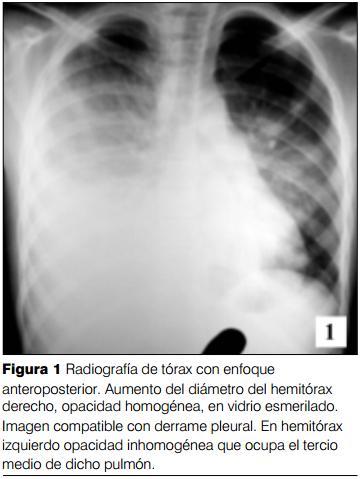

Niña de 12 años, raza blanca. Sin antecedentes personales patológicos. Inmunizada. Buen crecimiento y desarrollo. Comienza varios meses previos al ingreso con repercusión general, astenia, anorexia, adinamia y adelagazamiento. En las horas previas tos seca persistente, quejido, dolor tipo puntada en hemitórax derecho, polipnea y disnea. Radiografía de tórax: opacidad homogénea en hemitórax derecho con ocupación pleural líquida. Toracocentesis diagnóstica: 1.500 ml de líquido serohemático con las características de un trasudado. Cultivos negativos. No se deja drenaje. Se indican antibióticos intravenosos. Mala evolución, peoría clínica. Radiografía: compromiso bilateral y neumotórax izquierdo. Toracocentesis bilateral: 300 ml de líquido serohemático a derecha y 600 ml de líquido y aire a izquierda. Drenaje bilateral. Se traslada a la UCI en el postoperatorio inmediato. Al ingreso: lúcida, ventilación espontánea con máscara de flujo libre, saturometría de pulso 95%. Polipnea 48 pm, tiraje generalizada con retracción, balanceo. Síndrome de condensación a bronquio permeable en 2/3 inferiores de ambos hemitórax. Gasto de 300 ml por cada drenaje con las características descritas. Taquicardia regular 130 pm, PA 130/60/50 mmHg, pulsos presentes en los cuatro miembros y tiempo de recoloración inmediato. No visceromegalias.

Desde el punto de vista imagenológico (5,6) se observa en la radiología y en la tomografía convencional una infiltración de las partes blandas mediastinales, engrosamiento de los septos interlobares, derrame pleural y engrosamiento pleural que en ocasiones puede estar calcificado. Hay engrosamiento peribroncovascular e intersticial. Algunos pacientes tienen opacidades en vidrio esmerilado e infiltración perihiliar. En los casos de linfangiomatosis sistémica con compromiso pulmonar hay quistes que acompañan opacidades lineares en los pulmones (6).